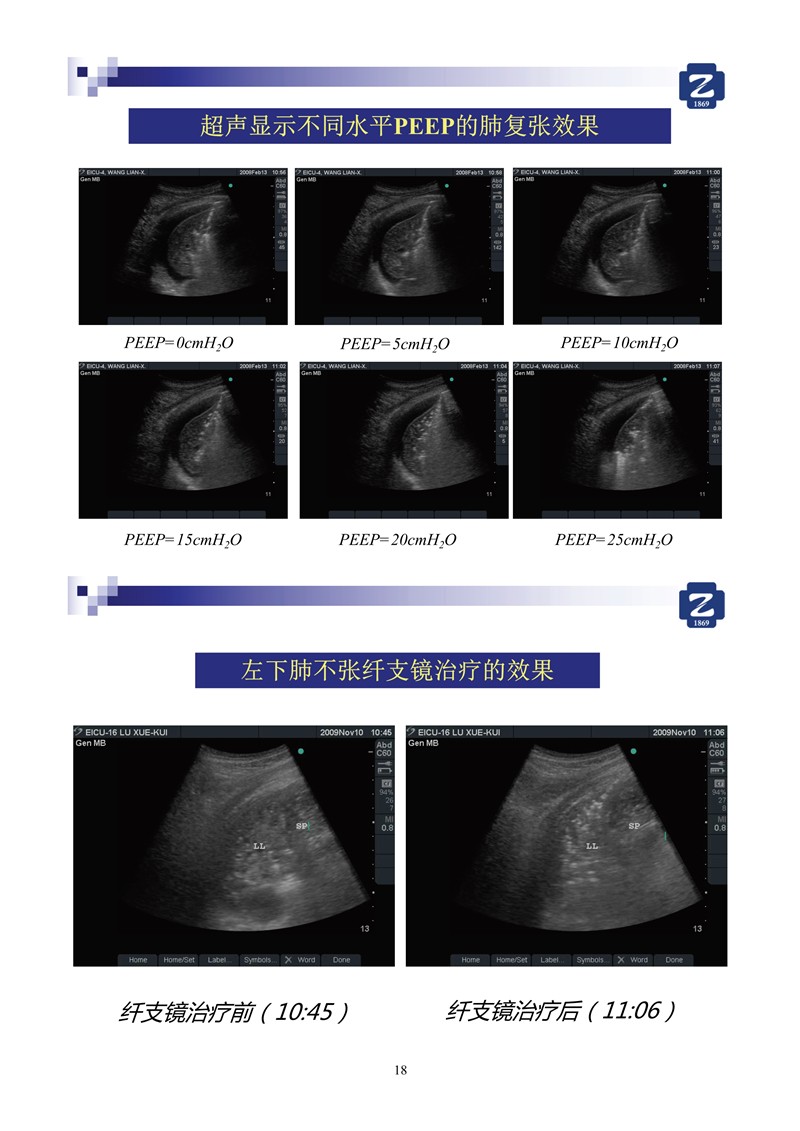

第一版新型冠狀病毒肺炎超聲診斷實(shí)用手冊(全文)